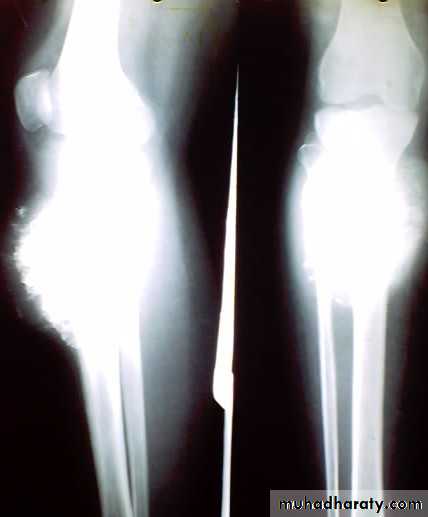

X-ray show eccentric osteolytic lesion in the end of long bone ,subchondral, trabeculated (soap bubble appearance). The cortex is thin, expanded or even perforated.